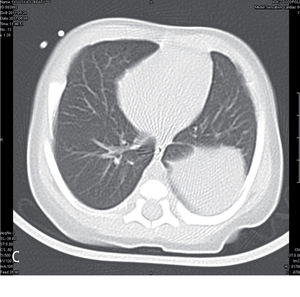

W piśmiennictwie medycznym większość publikacji na temat sekwestracji to zestawienia kilku do kilkunastu przypadków albo przeglądy piśmiennictwa.1,2,4,5 Największa przedstawiona grupa liczy 2625 chorych (zarówno dzieci, jak i dorosłych) i pochodzi z retrospektywnej analizy bazy danych, rejestrującej dobrze udokumentowane przypadki opisane w chińskim piśmiennictwie w latach 1998-2008.6 W tym materiale sekwestracje wewnątrzpłatowe stanowiły 84%, a zewnątrzpłatowe 16%. W obrazie radiologicznym sekwestracja przedstawiała się jako zmiany guzowate (46%), torbielowate (37%), jamiste (6%) lub naśladujące zmiany zapalne (10%). W obrazie tomografii komputerowej wysokiej rozdzielczości (HRCT) tych samych chorych uzyskano obraz zmian guzowatych (49%), torbielowatych (29%), jamistych (12%) lub naśladujących zmiany zapalne (8%) albo rozstrzeniowe (2%). U pojedynczych chorych zmiany miały obraz otorbionego wysięku.

Rozwój technik obrazowania umożliwia wykrycie wielu wad rozwojowych w życiu płodowym. Sekwestracja zewnątrzpłatowa może być uwidoczniona od 16 tygodnia życia płodowego. Widoczna jest w postaci ogniska hiperechogenicznego i stanowi około 16% ujawnianych w okresie przedurodzeniowym zmian płucnych. Wymaga różnicowania z gruczolakowatością torbielowatą płodu (cystic adenomatoid malformation), wrodzoną rozedmą miąższu płucnego, wadami serca, wrodzoną przepukliną przeponową, przetoką tchawiczo-przełykową, torbielami oskrzelopochodnymi czy zmianami rozrostowymi, takimi jak np. neuroblastoma umiejscowiona w śródpiersiu.1,7 Diagnostykę różnicową ułatwia zastosowanie ultrasonografii doplerowskiej8 i/lub rezonansu magnetycznego.9